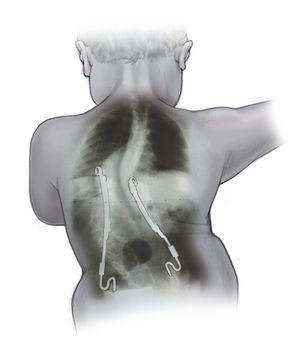

La indicación para la intervención fue en 16 casos una escoliosis congénita (figs. 24a-24c), en once casos una escoliosis neurológica y en doce casos una EIP. Las curvas se determinaron según Cobb. El ángulo de Cobb antes de la intervención medía un promedio de 65º (45-130º), y después de la intervención, un promedio de 32º (25-75º). En 18 pacientes tratamos una escoliosis torácica, en 18 pacientes una toracolumbar y en tres pacientes una lumbar (mielomeningocele). En 18 casos se utilizó un implante «costilla a costilla», en cinco casos un sistema de barra doble hasta la pelvis y en 18 casos un sistema híbrido (figs. 25 y 26).

Figuras 25a a 25c. a) Radiografía preoperatoria en proyección anteroposterior de una EIP con un ángulo de Cobb de 86º. b) Radiografía postoperatoria de una instrumentación «costilla a CL» realizada en una escoliosis toracolumbar progresiva. c) Radiografía postoperatoria en proyección anteroposterior después de 5 años. La curva se mantiene flexible y con buena corrección.

Realizamos un total de 39 implantes primarios, 102 cirugías de expansión y 24 sustituciones de implante. Estas últimas fueron necesarias debido a la aparición de curvas compensatorias o porque los implantes se habían quedado pequeños como consecuencia del crecimiento. Cada niño fue intervenido entre una y nueve veces (figs. 25a a 25c).